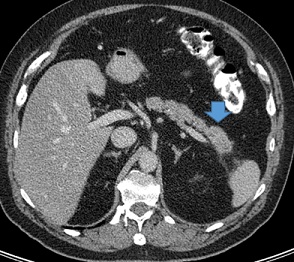

In 2017, in the lower lobe of  the left lung metastasis was found, the biggest one was about 11 mm in diameter (Figure 5). CA 19-9 was 404 kU/l (Figure 2). The combination a wedge resection and RFA was choosen as treatment and performed in October 2017. KRAS p. Gly12Arg and TP53 p.Arg306Ter tumor mutations were found after retrospective molecular diagnostics. 50 Gy (25 fractions a 2 Gy) radiotherapy of the thorax was also performed in 2018 as well as addivive chemotherapy with gemcitabine and capecitabine (6 cycles) from November 2017 until April 2018 and followed by GEM and capecitabine (4 cycles) from October 2018 until January 2019. Regular follow-up with tumor marker CA 19-9 showed once more a significant increase in January 2022 (form 31.4 kU/l up 167 kU/l in a year period of time) (Figure 2). In MR check up, a suspicious solid component was found in the lower lobe of the left lung (Figure 6), a biopsy was performed in Februar 2022. The histopatology showed fibrotic tissue without metastasis. At present the patient is doing well and is recurrence free. In his life the patient had some additional surgeries such as a radical prostatovesiculectomy due to adenocarcinoma Gleason-Score 6 (1998), epididymectomy (2014), osteoma resection frontal (1990, 2006), a benign tumor resection from left shoulder (2004), osteonecrosis resection right knee (1995) and lipomectomy on the neck (2016).

Figure 5: Axial images from a contrast-enchanced CT scans of thorax showing metastasis of a left lung.